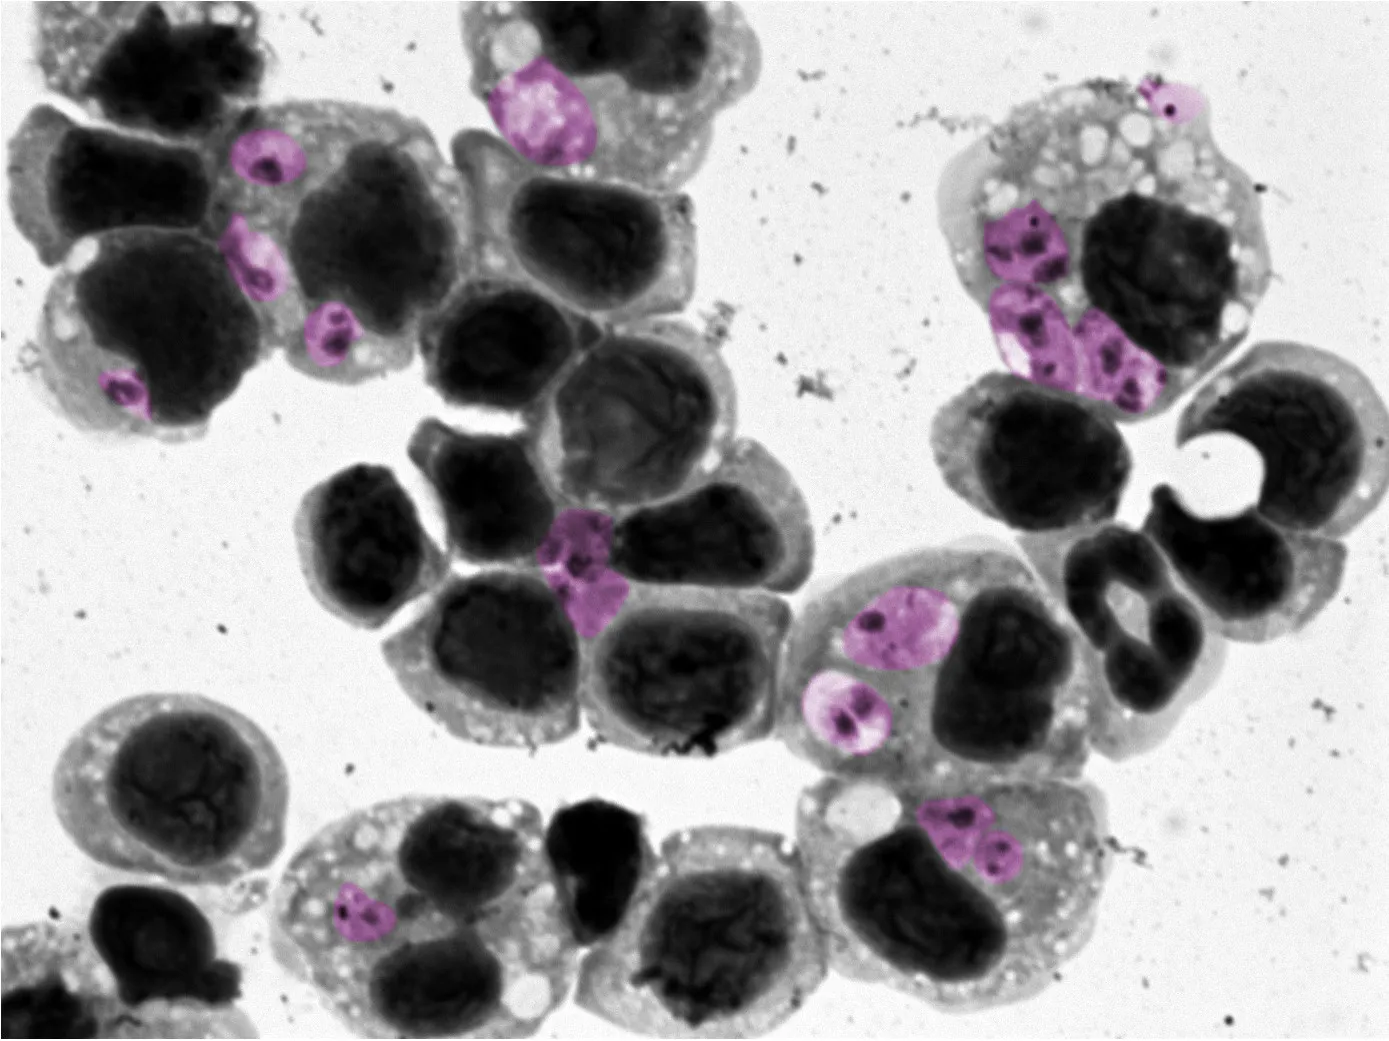

close-up of leishmaniasis

The Leishmania parasite under a microscope. Credit: David Mosser.